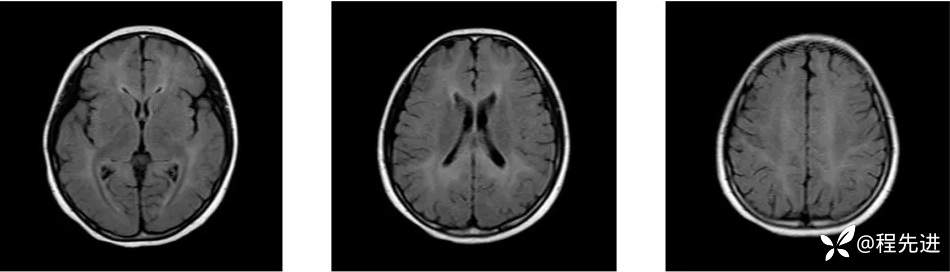

MRI: